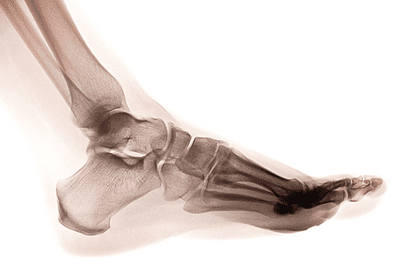

Heel spurs occur when a calcium deposit forms on the bottom of the heel bone. When viewed on an X-ray, heel spurs can extend out as much as a half-inch. Even without X-ray confirmation, many heel spurs can be identified during a physical exam.

Heel spurs occur when a calcium deposit forms on the bottom of the heel bone.